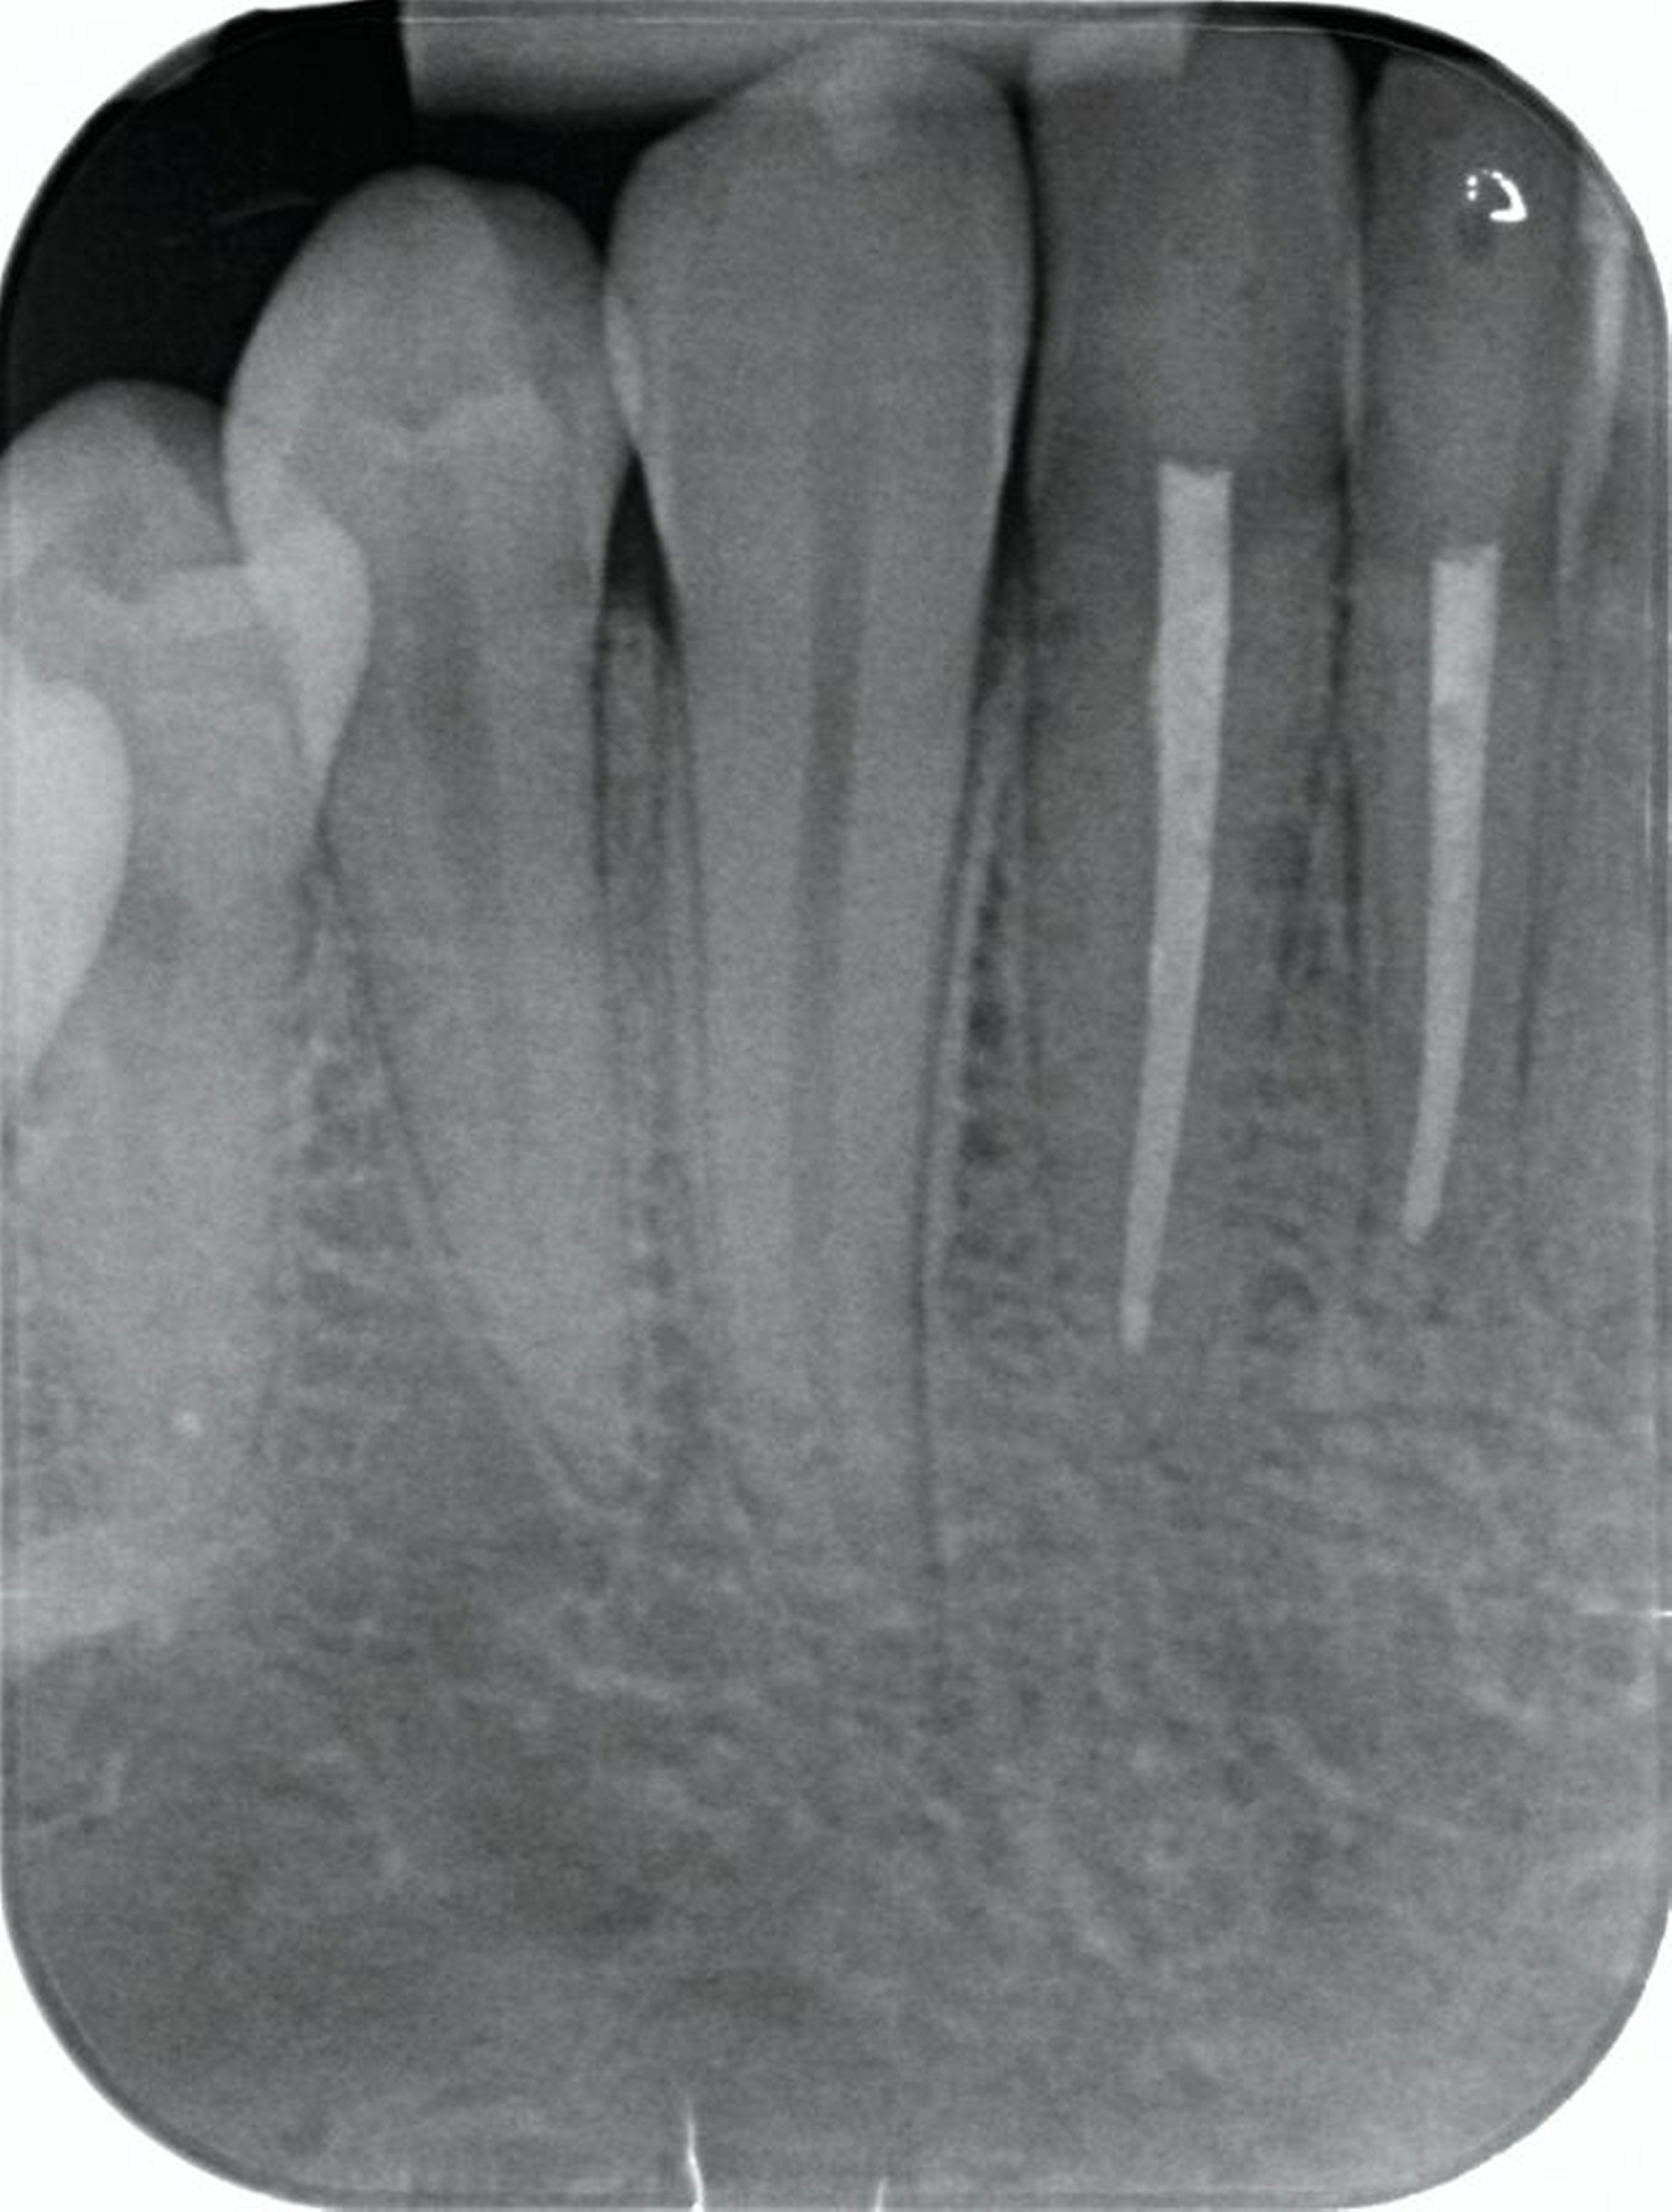

Zunächst wurden Einzelbildaufnahmen der Zähne 24, 26, 35, 33–43 angefertigt. Dabei fiel eine transluzente Frakturlinie ausgehend vom mesialen Parodontalspalt des 41 auf, die sich nach apikal-distal bis zum Apex des 42 darstellte (Abbildungen 3 und 4). Für einen radiologischen Überblick, mit dem auch eine Kiefergelenksfraktur ausgeschlossen werden kann, wurde eine Panoramaschichtaufnahme herangezogen (Abbildung 5). Darauf bildete sich eine unscharfe, C-förmige Transluzenz apikal der Zähne 31 und 41 ab. Eine genaue Beurteilung war nicht möglich, da der Bereich apikal der Unterkieferfront außerhalb der Bildebene lag. Die Processus coronoidei und condylares stellten sich beidseits unauffällig dar. Die Verdachtsdiagnose lautete: Unterkieferfraktur, unkomplizierte Kronenfrakturen an den Zähnen 26 und 35 sowie eine Längsfraktur an Zahn 24.

Laut dem radiologischen Befundbericht lag „eine nicht wesentlich dislozierte, paramediane Unterkieferfraktur rechts“ vor. Die Reposition und die Fixierung der Mandibula erfolgten am darauffolgenden Tag mithilfe von zwei Miniosteosyntheseplatten durch einen vestibulären Zugang in Intubationsnarkose. Die radiologische Kontrolle zwei Tage nach der operativen Versorgung ergab eine adäquate Stabilisierung der Fraktur durch die beiden Miniosteosyntheseplatten (Abbildung 7).